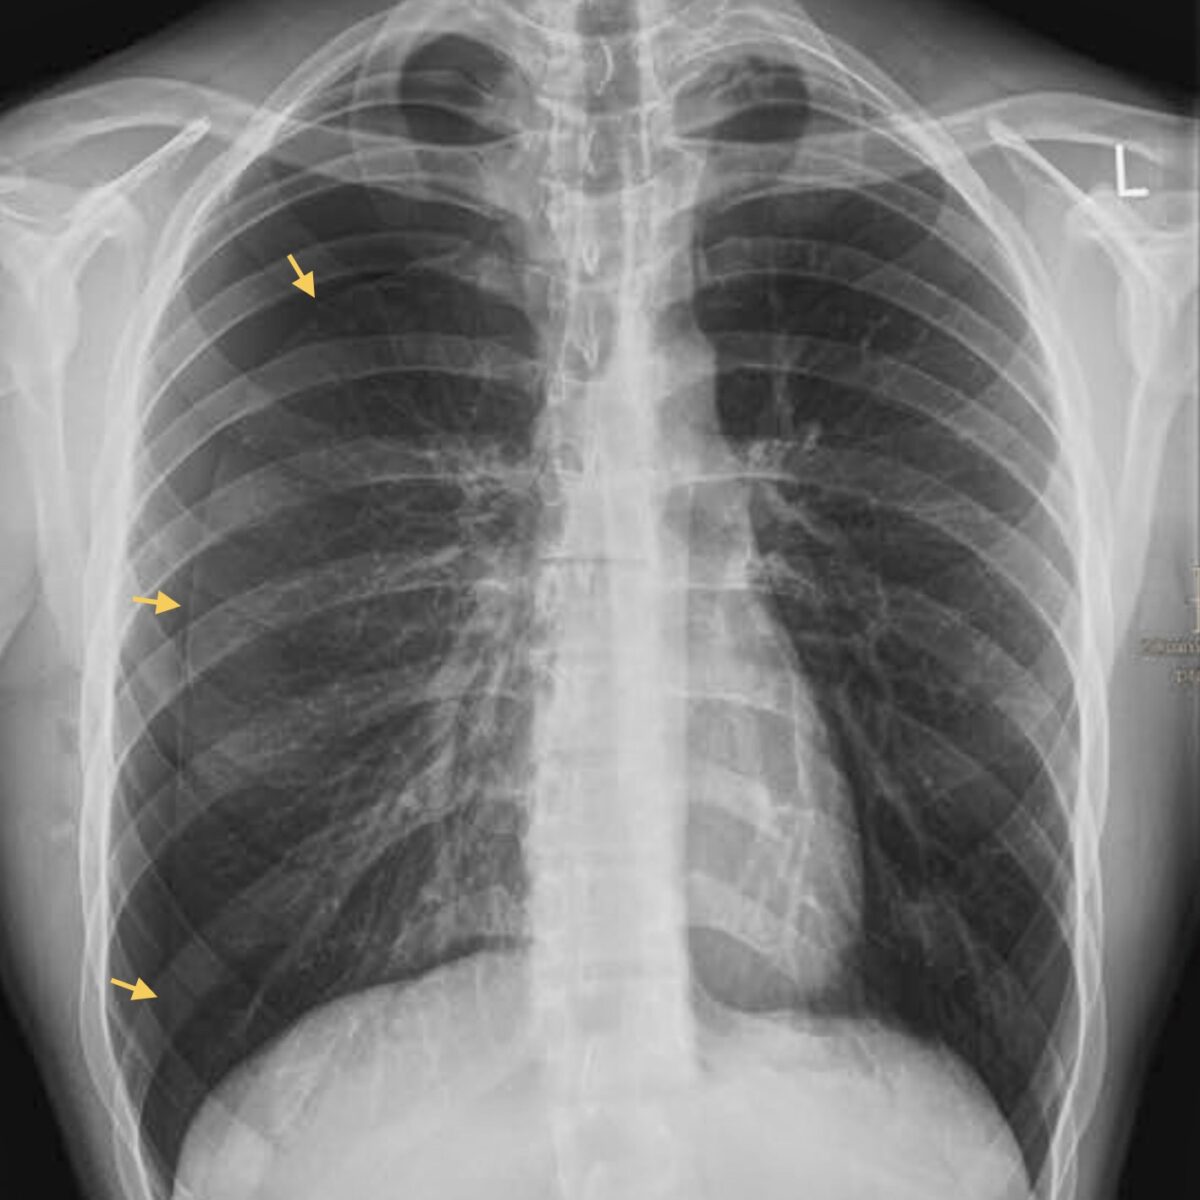

Wie wird ein Pneumothorax erkannt?

Die Diagnose erfolgt in der Regel rasch und zuverlässig mittels Röntgen oder Ultraschall. Bei unklaren Fällen kann eine CT-Untersuchung sinnvoll sein. Entscheidend ist, die Ausdehnung des Pneumothorax und mögliche Beschwerden richtig einzuschätzen, um die passende Therapie einzuleiten.